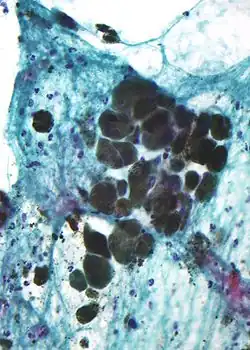

Microscopic appearance

Melanin is brown, non-refractile, and finely granular with individual granules having a diameter of less than 800 nanometers. This differentiates melanin from common blood breakdown pigments, which are larger, chunky, and refractile, and range in color from green to yellow or red-brown. In heavily pigmented lesions, dense aggregates of melanin can obscure histologic detail. A dilute solution of potassium permanganate is an effective melanin bleach.[53]